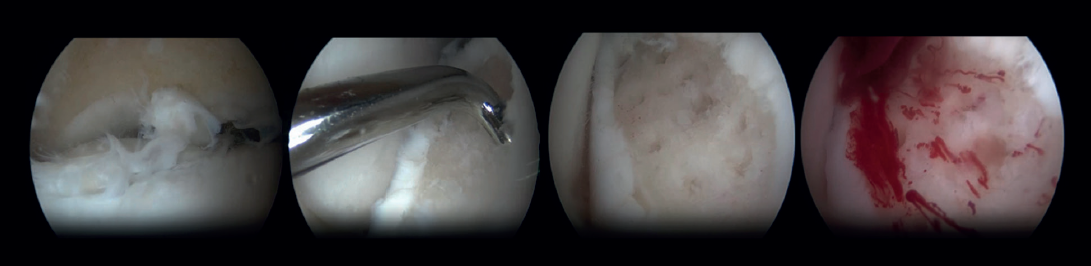

Arthroscopic Bone Marrow Stimulation (BMS) is the most frequently used treatment for primary OLT(22). BMS can be deployed for relatively smaller (<15 mm), non-cystic, non-fixable lesions(20,23). Arthroscopic BMS starts with debridement and curettage of the defective cartilage and subchondral bone(24). Subsequently, drilling or perforation of the sclerotic bone at the base of the defect is performed, often using a Kirschner wire or microfracture awl(25). The holes should be made to a depth that results in bleeding of the subchondral bone or the presence of fat droplets(23)(Figure 4). This technique disrupts the intraosseous blood vessels, leading to the subchondral bone bleeding and the formation of a fibrin clot. The release of mesenchymal blood cells promotes vascularization which induces the formation of fibrocartilage(26). When an isolated (i.e., no other damage to bone/within the joint) cartilage lesion with a macroscopically intact subchondral bone layer, is present, debridement only can be performed(27).

Bone marrow stimulation